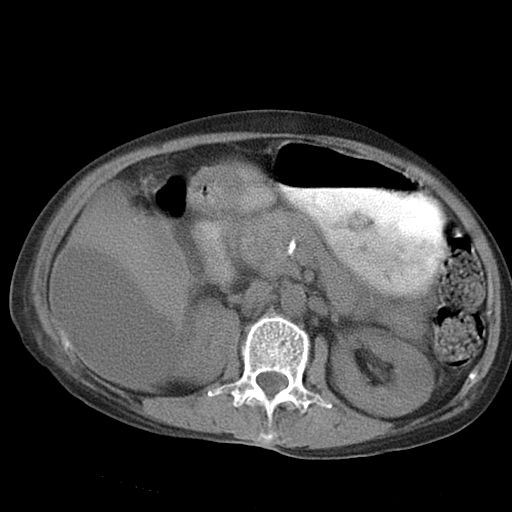

以下是引用dyqct在2006-12-7 21:08:00的发言:[br]考虑:1、肝内外胆管多发性结石伴肝左叶外侧段肝萎缩;[br] 2、右膈下多发脓肿;[br] 3、右侧少量胸腔积液、斜裂积液;[br] 4、左肾囊肿。

以下是引用jiazh在2006-12-7 20:37:00的发言:[br]肝脏周围半狐形低密度影,肝脏表面受压推移,考虑膈下脓肿可能性大;2、右侧胸腔积液

以下是引用拾荒者在2006-12-7 21:44:00的发言:[br]肝内外胆管多发结石,右膈下多发脓肿,右胸膜腔及叶间裂积液,左肾囊肿。[br] [br]